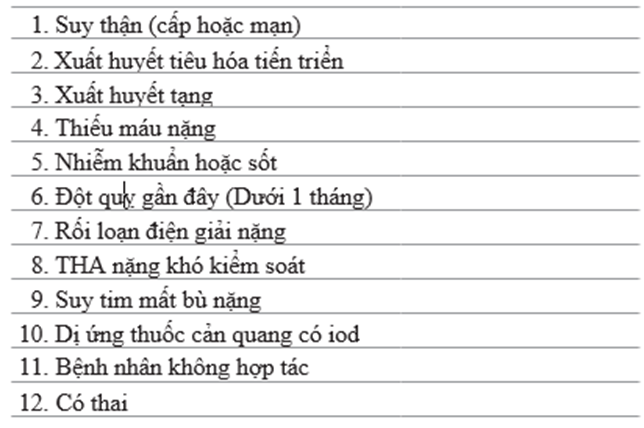

3. Chỉ định chính đặt thông tim ở người lớn là xác định giải phẫu mạch vành và mức độ hẹp của mạch vành. Thủ thuật có thể theo chương trình hoặc cấp cứu [5]. Table 71.2 tóm tắt chỉ định chính của chụp mạch vành. Không có chống chỉ định tuyệt đối với đặt thông tim. Table 71.3 tóm tắt các chống chỉ định tương đối

Table 71.3 chống chỉ định đặt thông tim